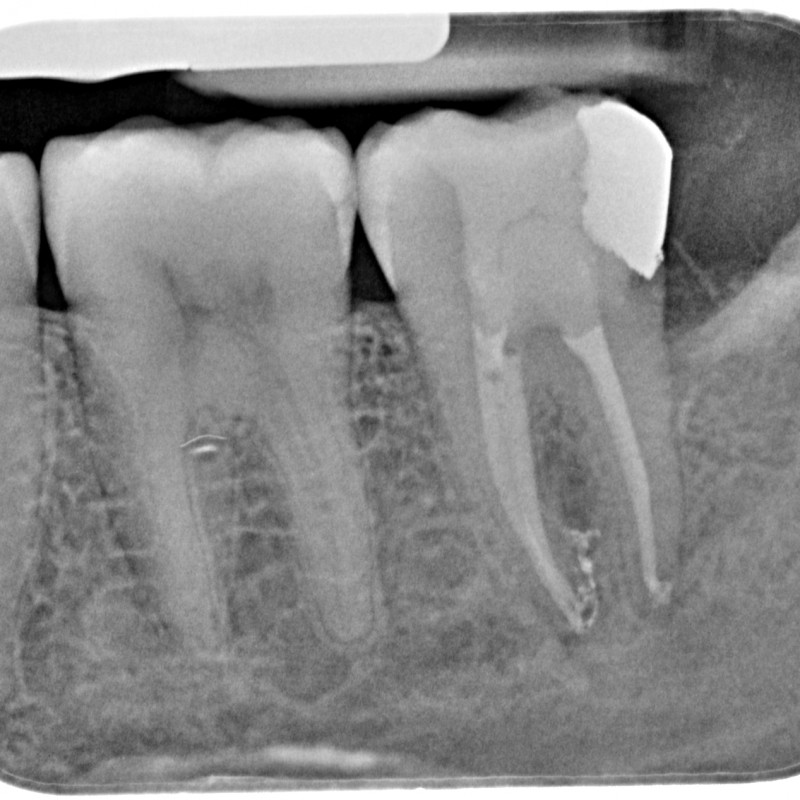

890205-14-5252-X-20150430-150718-XSYHD7J+NTN8-4